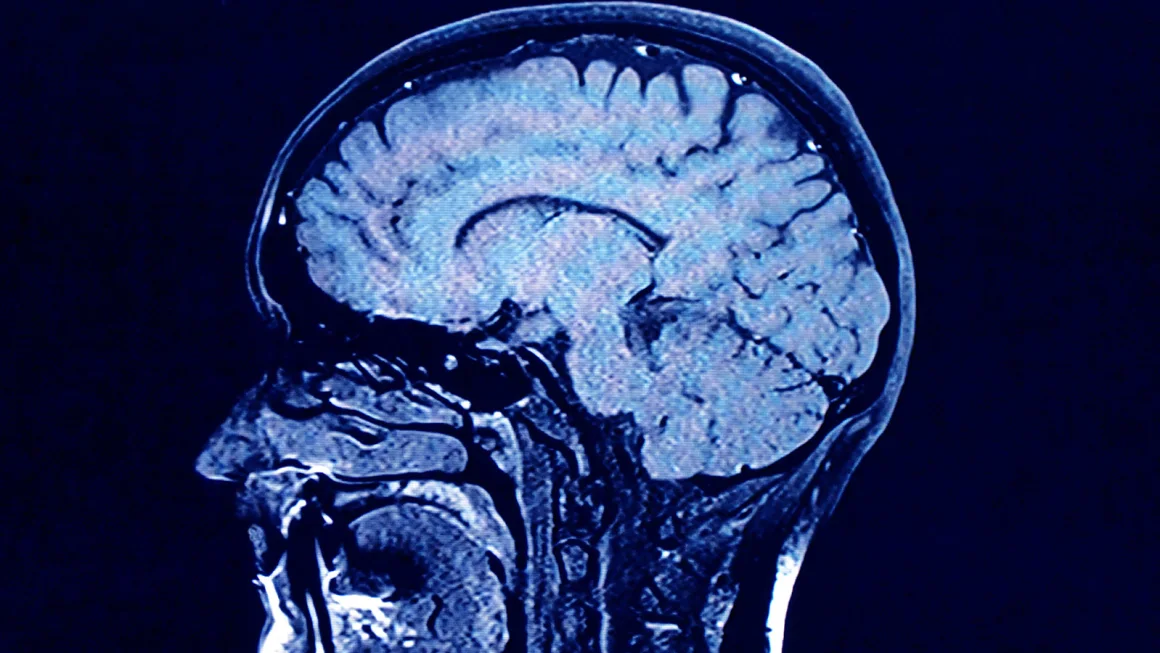

Дослідження Lothian Birth Cohorts включало дві групи людей: шотландців, народжених у 1921 і 1936 роках. У віці 11 років вони проходили тестування на когнітивні здібності, а пізніше, у 70, 80 та 90 років, проводилися нові тестування разом з МРТ мозку.

За словами Кокса, МРТ-сканування учасників показало велику різницю в здоров’ї мозку: у деяких людей мозок виглядав молодим і здоровим, а у інших спостерігалися значні зміни білої речовини, що пов’язано з когнітивним старінням та деменцією.